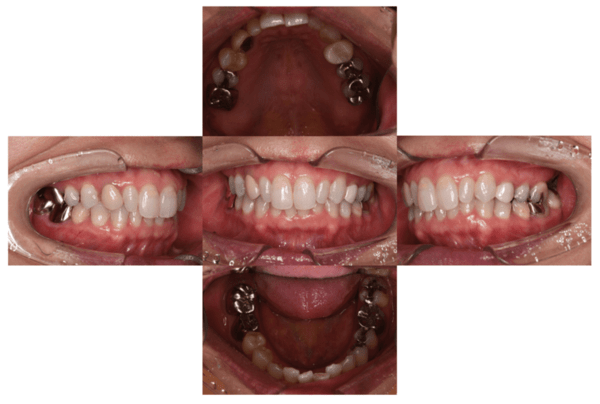

2022.7.9 経過観察後

口腔内写真

レントゲン写真

根管治療後3ヶ月です。根のまわりの骨がやや白くなってきているのがわかります。だんだん骨の添加がみられている証拠になります。

ここまで治癒していればかぶせ物をかぶせても問題ないと判断しました。

2022.8.13 クラウンセット

2022.10.16 予後経過

1年後 2023.3 予後経過

移植した歯はしっかり機能しており、問題なく使用できているとのことである。

最後のレントゲンでは、骨がしっかり添加され、周囲組織となんら変色ない状態にまでなっていることがわかる。